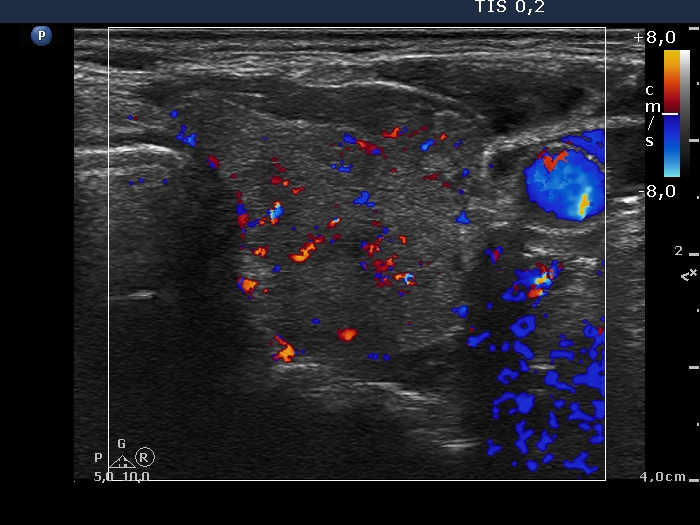

Right lobe, longitudinal scan

Left lobe, transverse scan, color Doppler mode. The vascularity is average.